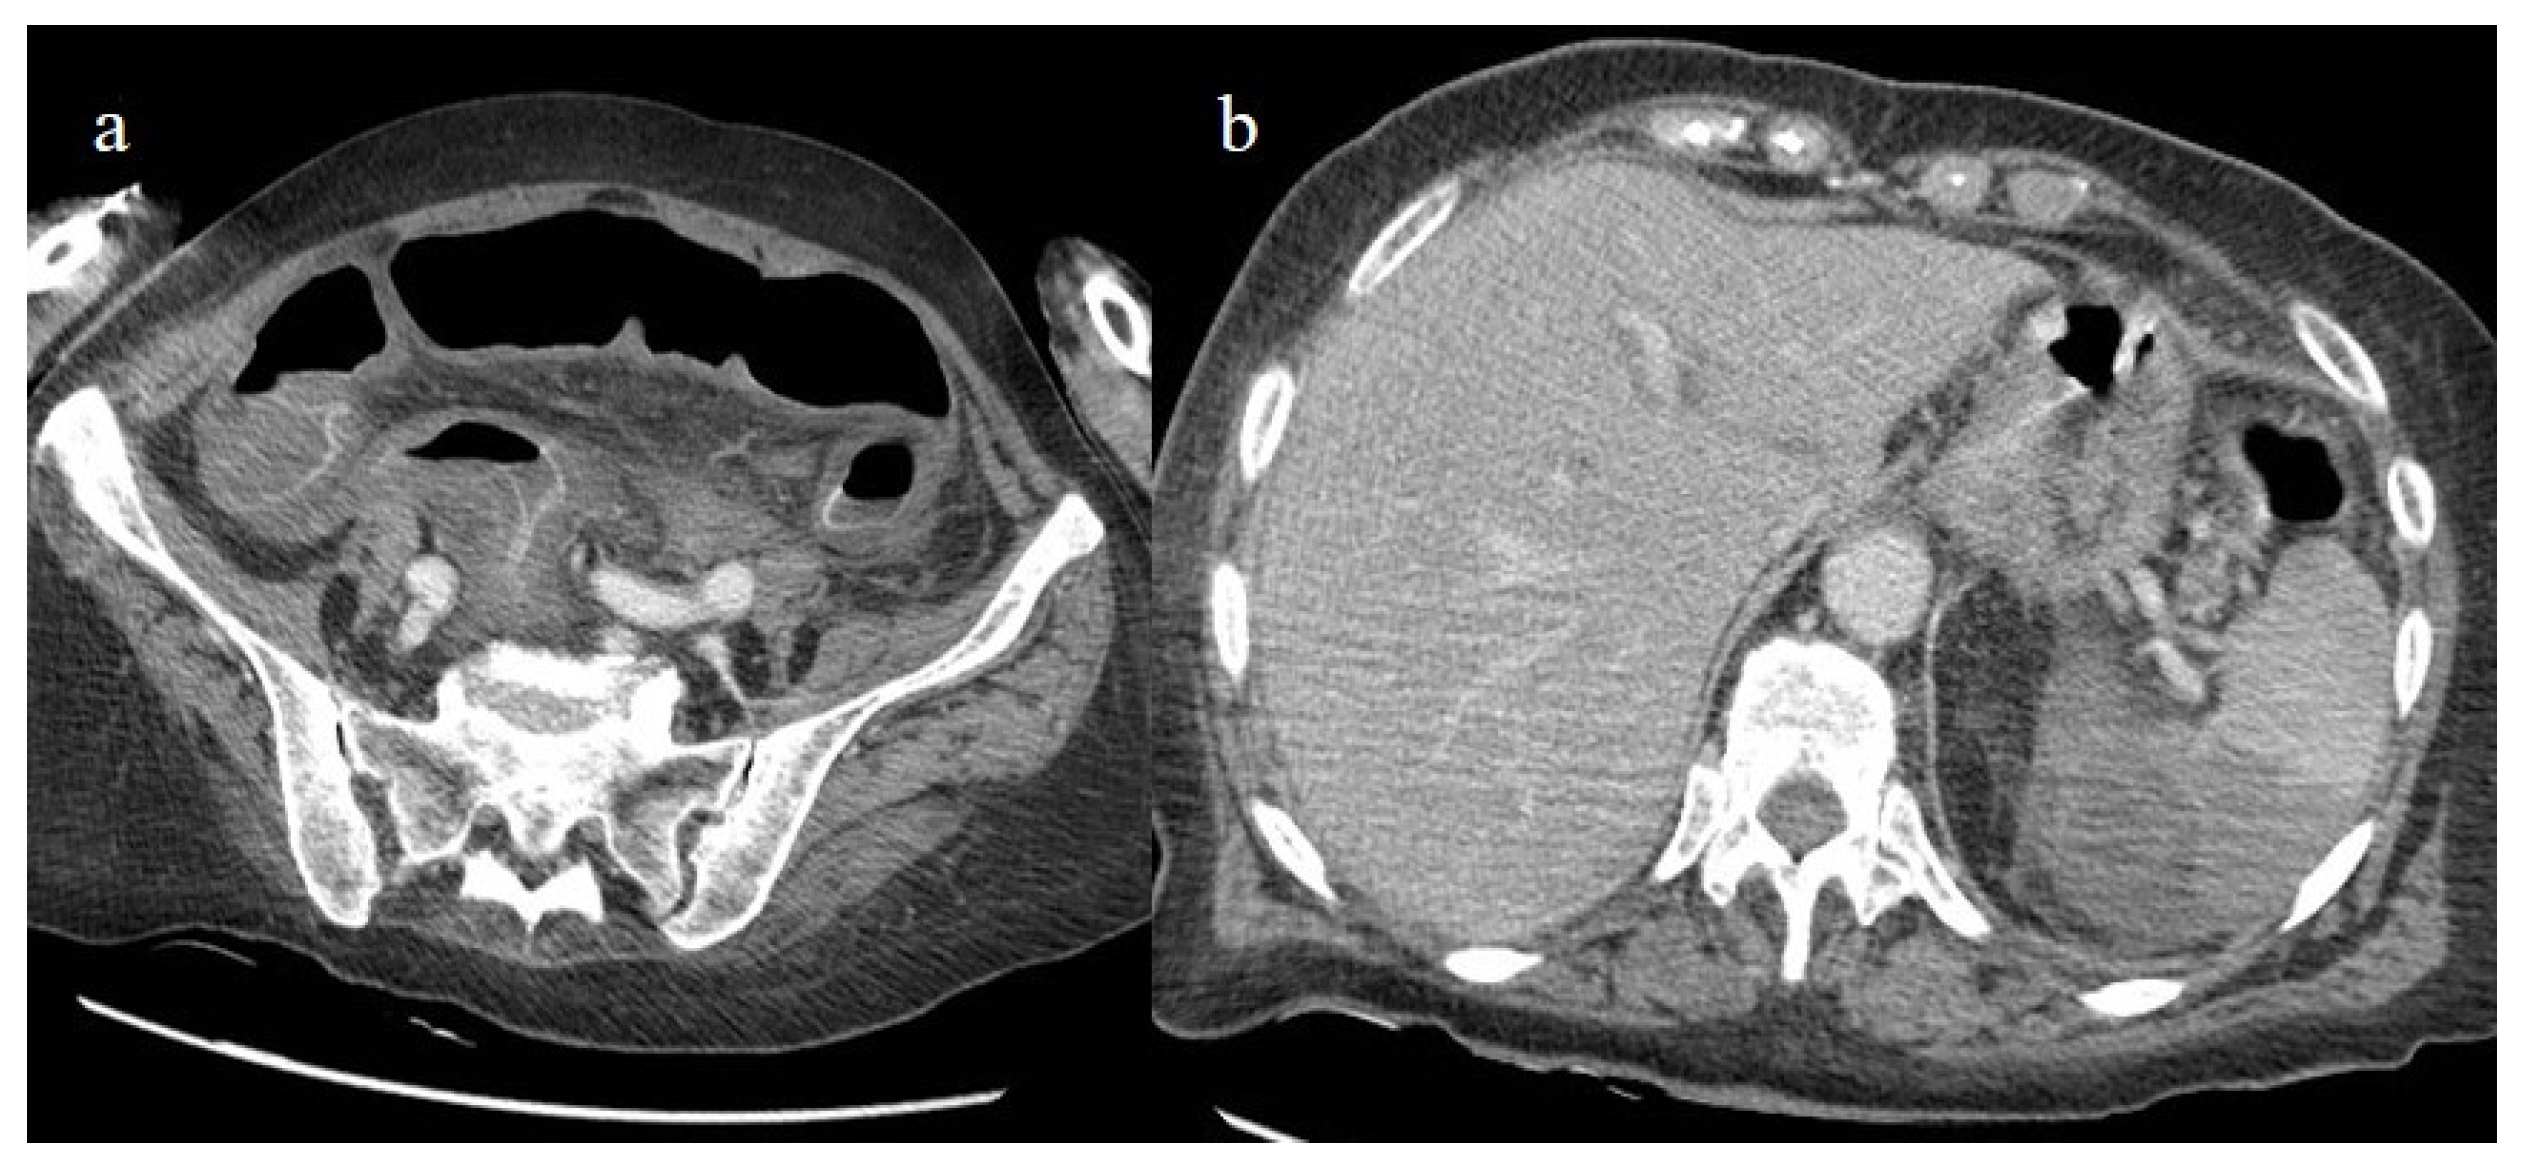

- Mahboubi-Fooladi, Z.; Arabi, K.P.; Khazaei, M.; Nekooghadam, S.; Shadbakht, B.; Moharamzad, Y.; Taheri, M.S. Parenteral Anticoagulation and Retroperitoneal Hemorrhage in COVID-19: Case Report of Five Patients. SN ComPract. Clin. Med. 2021, 3, 2005–2010. [Google Scholar] [CrossRef] [PubMed]

- Dubovský, M.; Hajská, M.; Panyko, A.; Vician, M. Severe Retroperitoneal Hemorrhage in a COVID-19 Patient on a Therapeutic Dose of Low Molecular Weight Heparin: A Case Report. Cureus 2022, 14, 26275. [Google Scholar] [CrossRef] [PubMed]

- Yeoh, W.C.; Lee, K.T.; Zainul, N.H.; Alwi, S.B.S.; Low, L.L. Spontaneous retroperitoneal hematoma: A rare bleeding occurrence in COVID-19. Oxf. Med. Case Rep. 2021, 2021, omab081. [Google Scholar] [CrossRef] [PubMed]

- Shah, M.; Colombo, J.P.; Chandna, S.; Rana, H. Life-Threatening Retroperitoneal Hematoma in a Patient with COVID-19. Case Rep. Hematol. 2021, 2021, e8774010. [Google Scholar] [CrossRef]

- Evrev, D.; Sekulovski, M.; Gulinac, M.; Dobrev, H.; Velikova, T.; Hadjidekov, G. Retroperitoneal and abdominal bleeding in anticoagulated COVID-19 hospitalized patients: Case series and brief literature abdominal bleeding in anticoagulated COVID-19 hospitalized patients: Case series and brief literature review. World J. Clin. Cases 2023, 11, 1528–1548. [Google Scholar] [CrossRef] [PubMed]

- Sposato, B.; Croci, L.; Di Tomassi, M.; Puttini, C.; Olivieri, C.; Alessandri, M.; Ronchi, M.C.; Donati, E.; Garcea, A.; Brazzi, A.; et al. Spontaneous abdominal bleeding associated with SARS-CoV-2 infection: Causality or coincidence? Acta Biomed. 2021, 92, e2021199. [Google Scholar] [PubMed]

- Mahmoudabadi, H.Z.; Hadadi, A.; Fattahi, M.R.; Kafan, S.; Ashouri, M.; Allahbeigi, R.; Hajebi, R. Rectus Sheath Hematoma in COVID-19 Patients as a Mortal Complication: A Retrospective Report. Int. J. Clin. Pract. 2022, 2022, 7436827. [Google Scholar] [CrossRef]

- Maruyama, S.; Wada, D.; Oishi, T.; Saito, F.; Yoshiya, K.; Nakamori, Y.; Kuwagata, Y. A descriptive study of abdominal complications in patients with mild COVID-19 presenting to the emergency department: A single-center experience in Japan during the omicron variant phase. BMC Gastroenterol. 2023, 23, 43. [Google Scholar] [CrossRef]